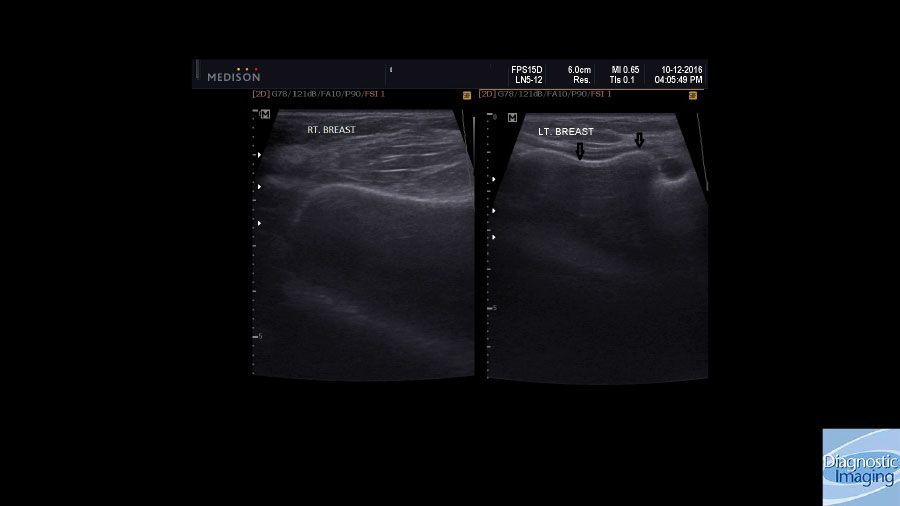

Case History: 28-year-old female with left breast pain and swelling two years after augmentation mammoplasty.

Case History: 28-year-old female presented with left breast pain, swelling, and hard feeling of her breast implant two years after augmentation mammoplasty.